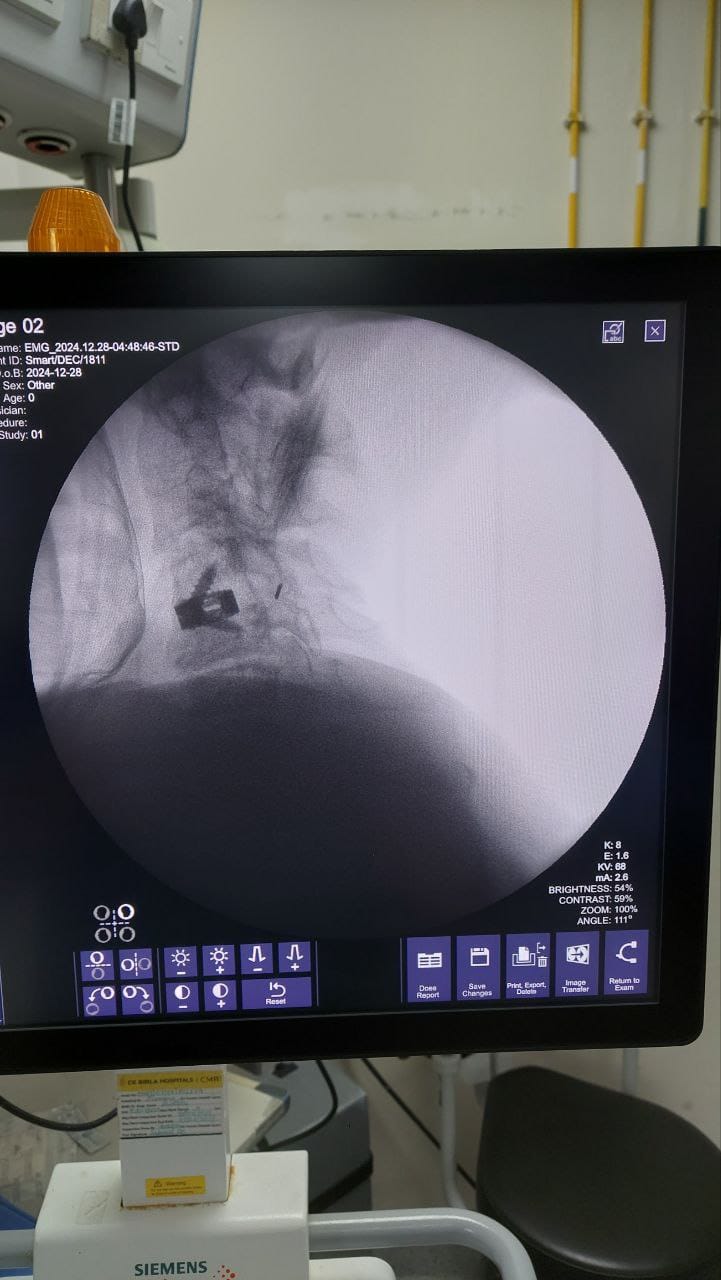

Procedures

Struggling with chronic pain? Get advanced, personalised pain management from Dr. Manish De, one of Kolkata’s leading pain specialists. From knee pain, heel pain, low back pain, frozen shoulder, migraines, cancer pain to post-TKR persistent pain—Dr. De offers safe, evidence-based treatments across multiple locations: